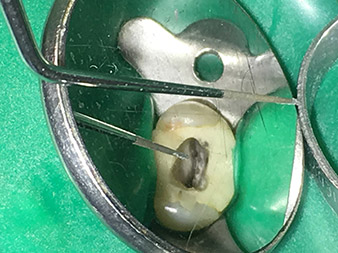

Efficient and atraumatic root canal treatment

As an avid user of the expanded W&H instrument range for ultrasonic endodontics, Dr Nouraie Ashtiani is not only able to perform root canal treatments more efficiently but also to do so in a way which puts less strain on the patient. The dental expert masters even the most difficult of situations with ease. In a recent interview, the specialist in endodontics told us about the particular features which characterize the W&H instruments and mentioned possible risks which can arise in root canal treatment.

Dr. Nouraie: Yes, in my opinion. The tips allow you to work in a particularly atraumatic and minimally invasive manner. Among other steps, this applies to the exposure of the individual canal accesses, preparation of the cavity in the area of the pulp chamber, rounding off of the canal openings at the transition from the bottom of the chamber to the root canal and preparation of the coronal regions of the root canals.

It is also possible to activate the rinsing fluid in the root canal system. What’s more, it makes a range of special indications such as the revision of broken-off instruments and root posts possible.

Dr. Nouraie: I particularly enjoy working with the 1E tip. It is perfectly suited to activating the rinsing fluid in the root canal system. The delicate design of the tip allows you to reach deep sections of the canal too and ensure optimal activation.

Dr. Nouraie: The use of ultrasonic tips allows targeted, atraumatic, minimal removal of substance at the desired site (e.g., when exposing the canal openings, rounding off the cavity floor and exposing broken-off instruments or posts as well as when processing coronal canal sections).

Canal transitions can be smoothed and rounded off with more precision than when using burs. The activation of the rinsing fluid in particular offers enormous advantages that cannot be guaranteed with other instruments. The special instruments from W&H make it possible to perform completely new indications minimally invasively such as revision of broken-off tips and posts.